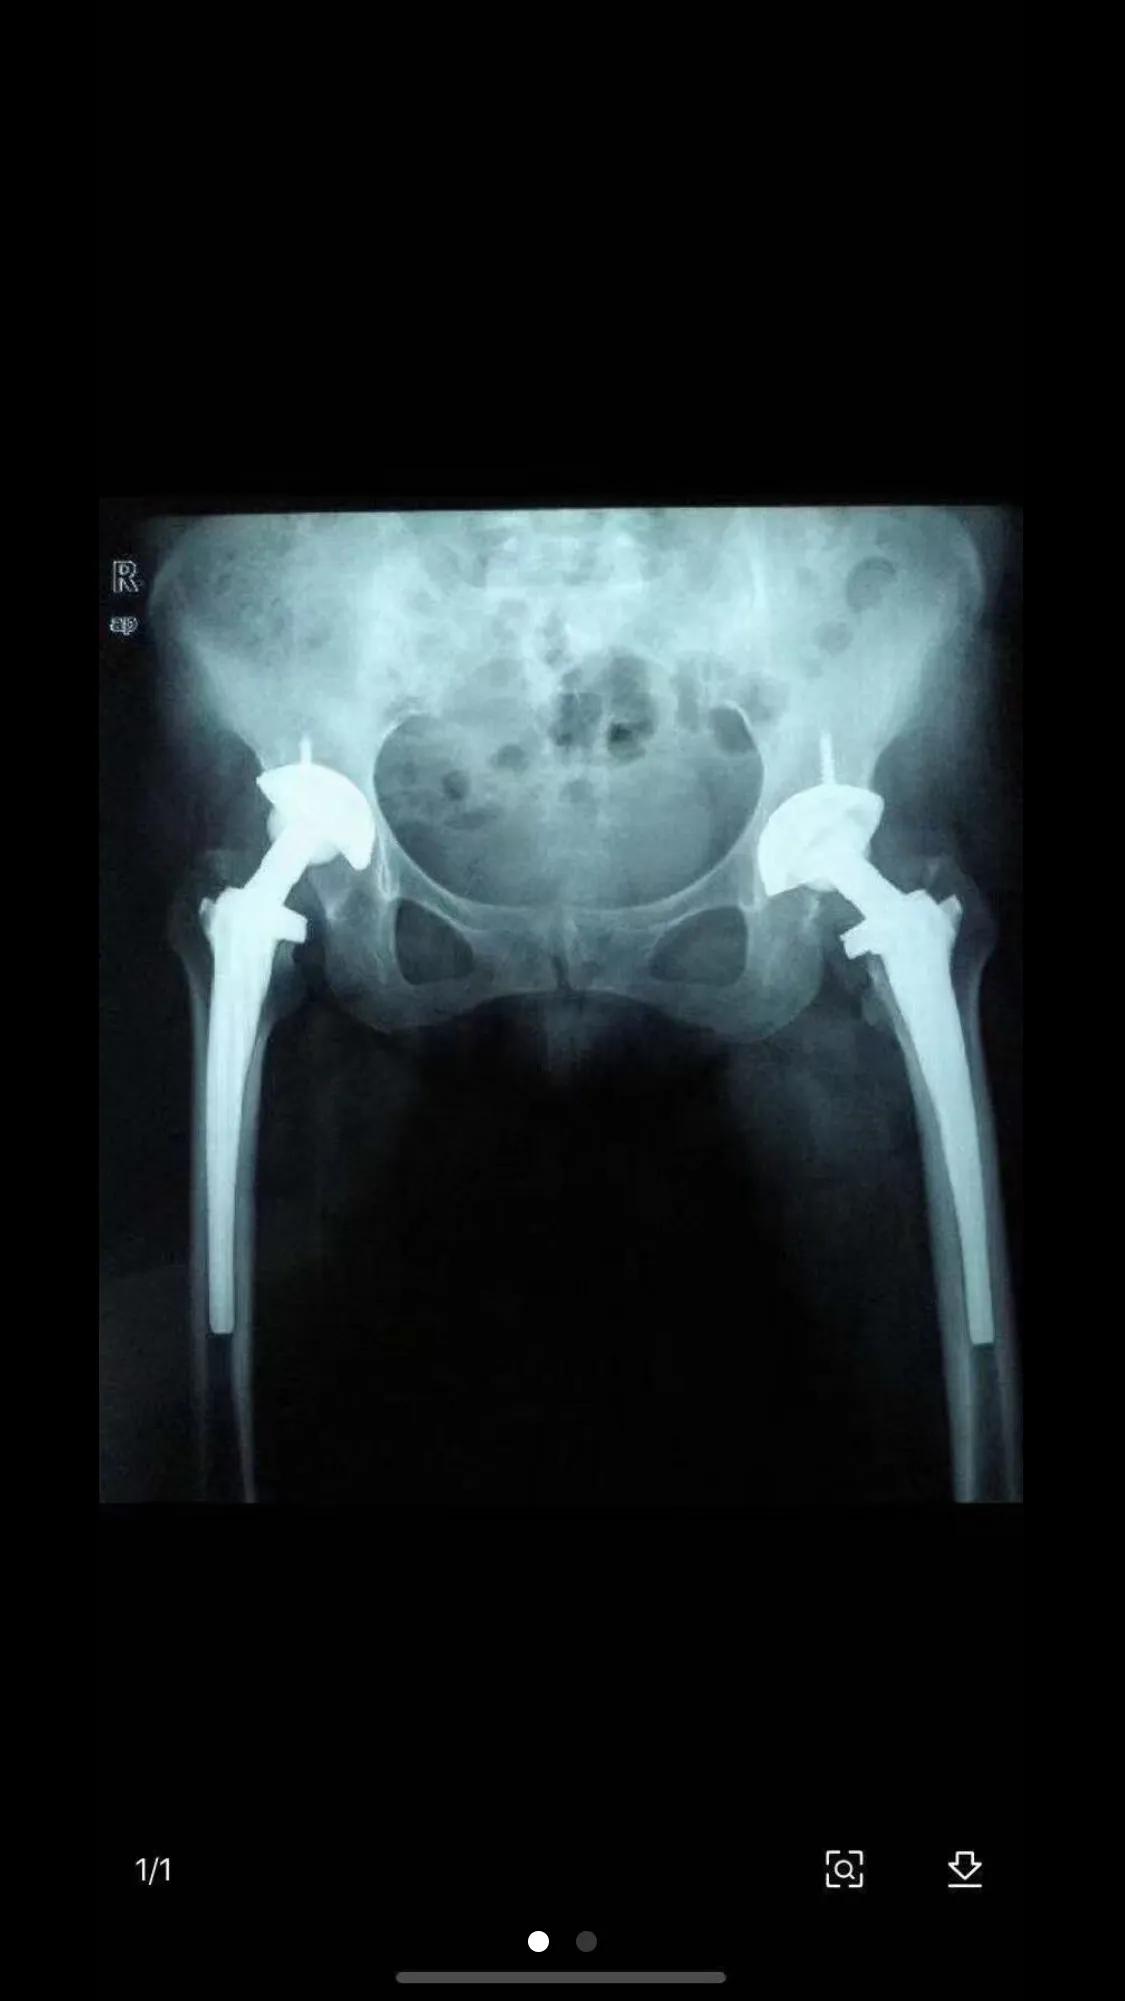

203医院骨科是全齐齐哈尔市和黑龙江省西部地区技术最好的科室,住院患者聚增,一床难求,除本市外,还有内蒙古自治区各旗和吉林省各地区患者慕名来203医院骨科求医,科室病房走廊天天加床,有时住院患者120多人,加床40多张,科室医生少,手术量大,我进修二个多月后,科室决定让我独立管理病人,给处方权,按照本科医生对待,仍由孙道植老师和各位老师负责带教。自己管理床位十六张,王光华副主任负责排手术,为了让我更好更快学习手术技能,在手术日排手术时,经常给我多排一例手术。我在创伤病区进修八个月后转骨病区,仍然是独立管理患者,由王海波老师负责带教,随着时间推移,我在各位老师的带教指导下,逐渐能完成颅骨牵引、胫骨髁上、跟骨牵引,气管切开术,复杂肌腱神经断裂吻合术,四肢创伤骨折切开复位,钢板固定术和梅花针,V型针固定术,肱骨外上髁骨折,切开复位克氏针固定术。还同老师同台手术当一助,如先天性髋关节脱位,骨盆截骨克氏针固定➕石膏固定术,股骨头坏死,全髋植换术,人工踝关节植换术,人工肌腱移植术,腰椎间盘脱出髓核摘除手术,骨结核病灶清除植骨术、骨肿瘤截肢术,各种骨病矫形术,骨延长术,皮瓣移植术等。